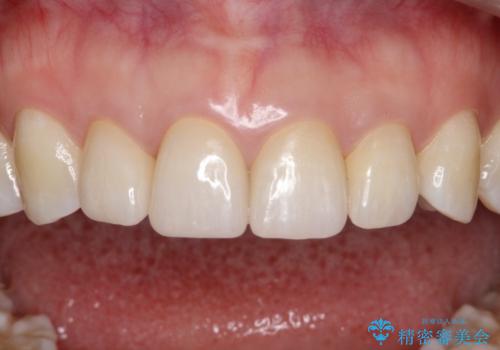

【精密根管治療+オールセラミッククラウン】より自然な前歯にしたい!

- 他院で治療した前歯が白すぎること、時々ズーンと痛むことを主訴に来院されました。

根っこの先端に病気も見つかったため、根管治療からやりかえて治療を行なっています。

被せ物の製作時は、患者さんと技工士さんが直接話をすることで、より満足度の高い治療を行うことができました。